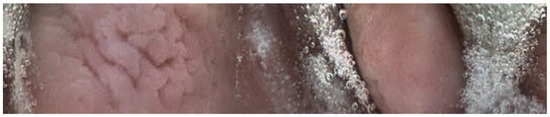

When administered for the determination of GET, SITT, and OCTT, the transit times recorded from retrieved capsule time-stamped images were used to compare the transit times between treatment groups, as previously reported [17]. The serial number of each video capsule in each study period was recorded to ensure the accurate identification of the capsules. Following the collection of the video capsules, the video recordings from each capsule were downloaded and randomized (Excel Randomization). The time points when a capsule moved from the stomach to the duodenum (GET) and from the duodenum to the cecum (SITT), and the overall time from the stomach to the cecum (OCTT) were recorded for each capsule video by three blinded researchers (M.E.P., C.R.B., S.H.B.). The observers were trained to identify each particular segment of the GIT using previously published images of the stomach, small intestine, and cecum mucosa.

Twenty-seven of the forty-five capsules that were administered to the horses were able to be successfully recovered from feces (n = 24) or in a post-mortem examination (n = 3). One of the twenty-seven capsules (control capsule #1) did not move from the stomach for the entire battery life of the capsule (Figure 1). Twelve of the twenty-seven capsules (bit-chewing capsule #8–10,12,13,15; control capsule #4,5,7,10,11) did not pass through the ileocecal orifice during the battery life of the capsule. The battery life of the endoscopy capsules ranged from 7.8 to 22.7 h. Of the video endoscopy capsules that were recovered, the time to recovery (mean, median, and range) in the manure was as follows: 11.14 days, 6.45 days, and 2.25–43 days. No video endoscopy capsules were recovered within 21 days from three horses; these horses were excluded, and the study was repeated with three different horses. The capsules were not difficult to use, and the transitions from the stomach to the duodenum and from the ileum to the cecum were easily identifiable with fair-to-excellent interobserver variability between the three blinded observers (Figure 2, Figure 3 and Figure 4). The coefficient variants were excellent for GET (CV = 0.98, n = 26 capsules, six horses), fair for SITT (CV = 0.36, n = 14 capsules, six horses), and good for OCTT (CV = 0.79, n = 14 capsules, six horses).

Figure 2. Picture obtained from endoscopy capsule within the small intestine. Note the “carpet-like”-appearing villi present within the small intestine compared to the more corrugated appearance of the stomach. An additional endoscopy capsule is also in the picture.